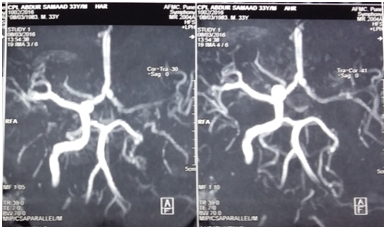

Before shifting patient to operation theatre, a repeat MR Angiography was done to ensure that there is a stable thrombus at the injury site before pack removal. It showed an ill defined hypodense areas involving gray and white matter in left frontal and parietal lobes in the region of ACA-MCA and MCA-PCA watershed territories respectively, suggestive of watershed territory infracts. Ill defined hypodense areas suggestive of infracts are seen in left centrum semiovale in vicinity of central sulcus (Figure 2) and loss of signal intensity in petrous, cavernous and supraclival part of left ICA (Figure 3). Nasal pack removed under GA with no re-bleeding from injured site. Clot was seen over the injured part of ICA in the left sphenoid sinus plugging the LT ICA (Figure 4). Postoperative antiplatelet therapy continued augmented with physiotherapy.

Figure 2 MR Angiography showing ischemic infarct in ACA-MCA & MCA-PCA watershed territory left side.

Figure 3 MR Angiogram showing loss of signal in petrous, cavernous and supraclinoid segment of left ICA.